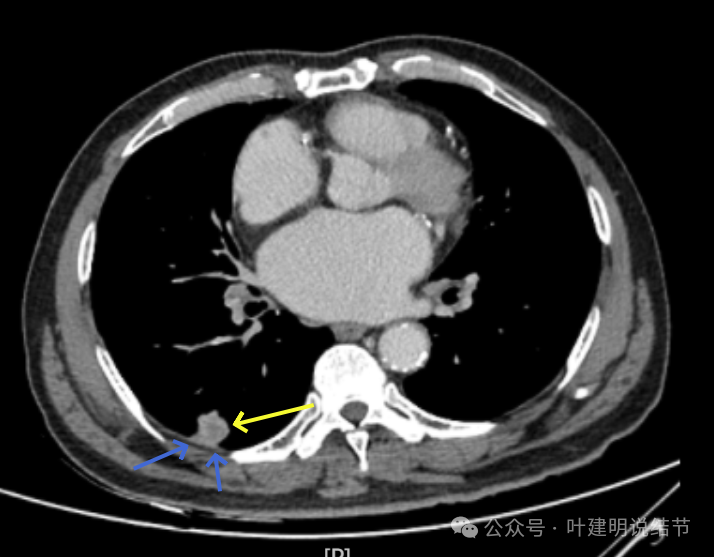

增强纵隔窗见病灶内部的密度好像低于周围区域,像坏死。

邻近胸膜无牵拉,灶内有低密度区,局部有点状液性密度。邻近胸膜较为广泛的增厚或胸膜反应。

病灶与胸膜接触面宽,病灶内部密度较低。